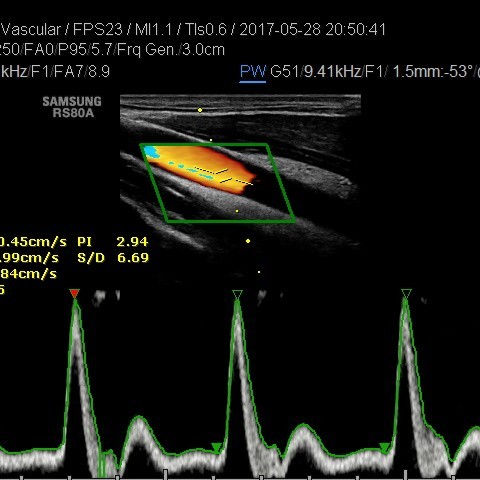

• USG tętnic szyjnych i kręgowych

• USG doppler tętnic kończyn górnych i dolnych

• USG doppler aorty i naczyń biodrowych

• USG doppler układu wrotnego